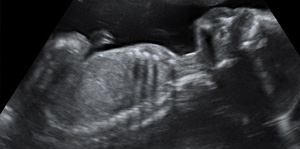

En la semana 21 de embarazo el crecimiento del útero ya es evidente. La musculatura abdominal de la madre se adapta al bebé que se desarrolla en su interior. El pequeño se sigue moviendo a sus anchas y absorbe nutrientes del líquido amniótico que le rodea.

- El feto de 21 semanas de embarazo pesa unos 300 gramos y mide unos 18 centímetros. En este momento, el crecimiento ya no es tan rápido como en las semanas anteriores.